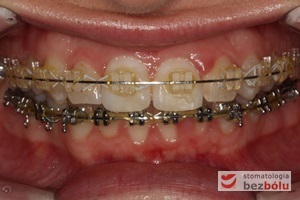

Pacjentka lat 22 zgłosiła się do naszej placówki celem podjęcia leczenia ortodontycznego. Głównym oczekiwaniem pacjentki była poprawa estetyki uśmiechu oraz brak ekstrakcji zębów na drodze do jej uzyskania. Ze względu na liczne stłoczenia zębów w górnym i dolnym łuku, dość duży materiał zębowy w porównaniu z bazą kostną, a także zgryz przewieszony boczny prawostronny po dokładnej analizie cefalometrycznej oraz analizie modeli diagnostycznych zastosowano leczenie bezekstrakcyjne z wykorzystaniem strippingu jako alternatywy dla usuwania zębów, mającego na celu uzyskanie miejsca w łuku na uszeregowanie zębów. Po fazie aktywnego leczenia trwającego 18 miesięcy zastosowano leczenie retencyjne w postaci szyny retencyjnej w łuku górnym oraz retainera stałego w łuku zębowym dolnym klejonego od kła do kła.